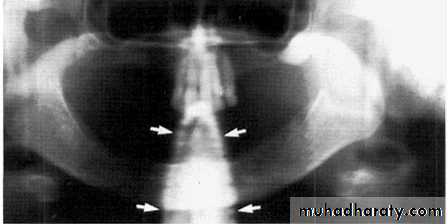

Stud earrings, real shadows (solid arrows)

with ghost shadows (open arrows).Tongue bar projected over palate